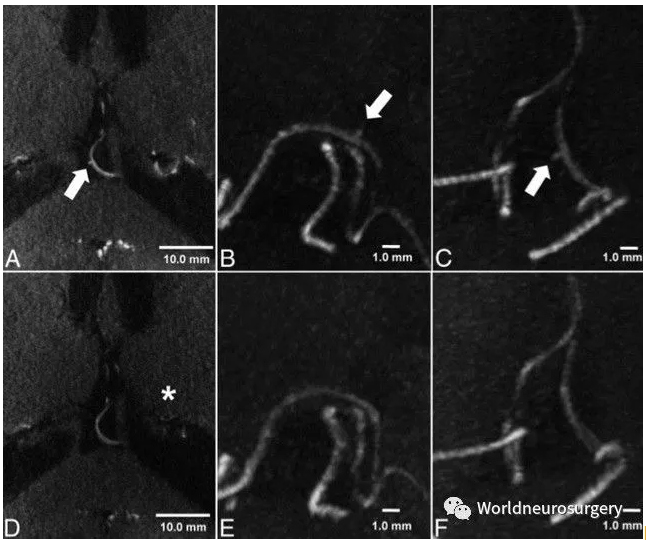

同一患者的7T磁共振TOF-MRA影像。

肌萎缩侧索硬化

上排为健康对照组,下排为ALS患者的SWI图像。